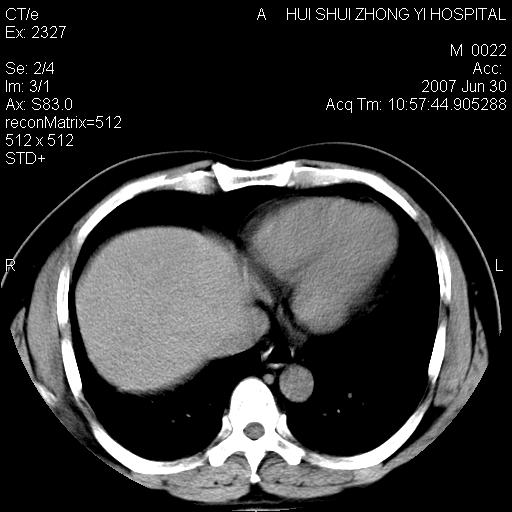

男,44岁,体检。

双侧肾盂、输尿管内结石,双侧肾脏轮廓呈波浪状,可能以前有过感染的

支持双肾结石,肝右叶低密度影为胆囊部分容积效应。

肝右叶低密度影为胆囊部分容积效应?为什么s43.0层面下来不见胆囊影,而是相隔了一层才见胆囊影。这是按我们扫描的顺序发的,但是是追加扫描的。

病人呼吸动了,第四层应该在第五\\六层之间。肝右叶低密度影为胆囊部分容积效应。双肾结石。

考虑:1、水平肝;

2、双侧肾盏结石。